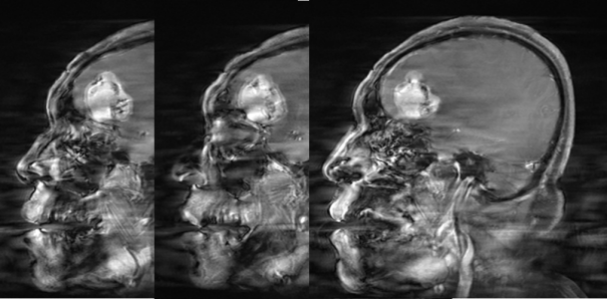

CASE 4

男,62 岁

右侧顶叶区混杂信号占位,T1、T2 内部条样低信号影,血管留空信号;增强可见明显强化,内部信号欠均匀,内见强化迂曲血管影。

诊断:右侧顶叶区血管外皮瘤